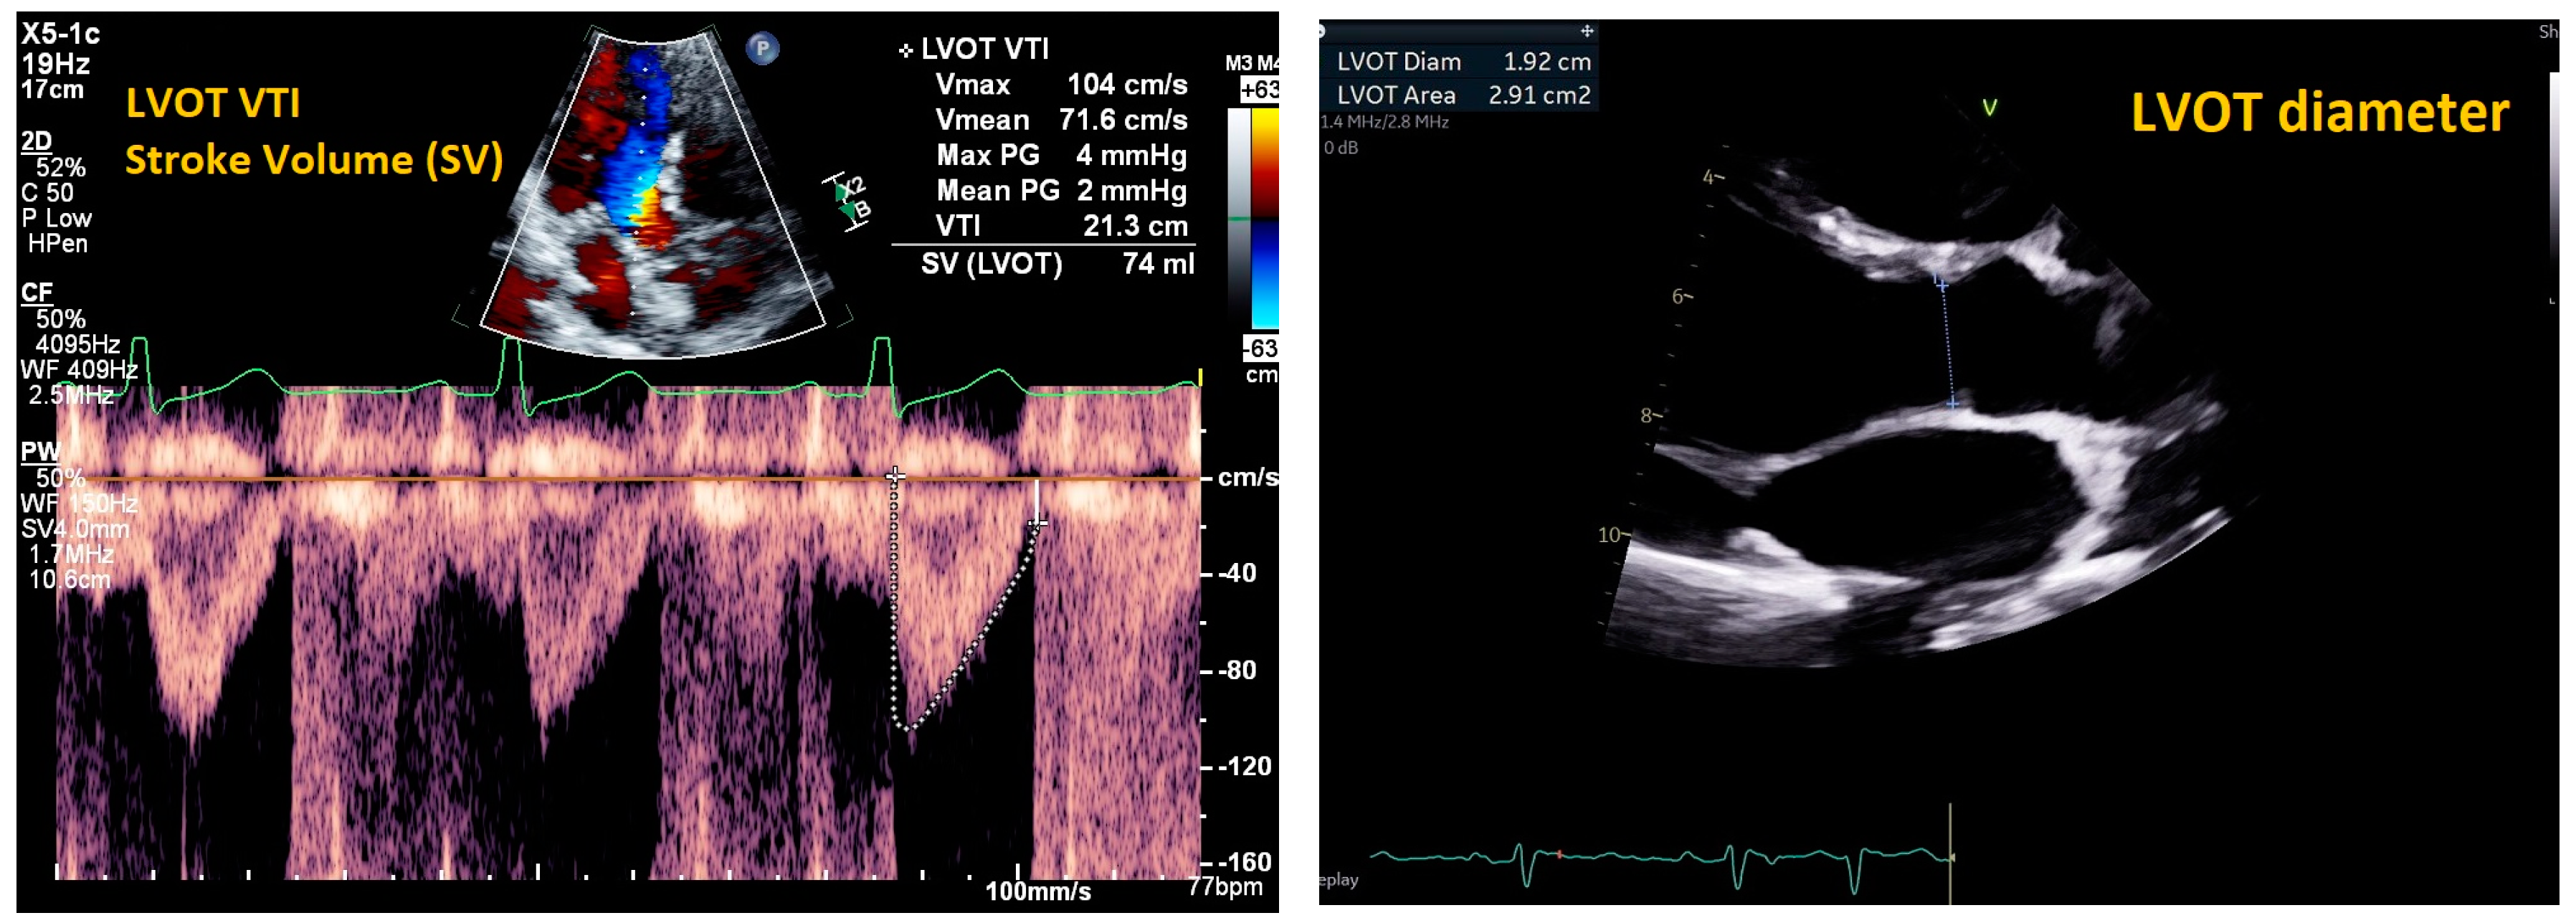

| Cardiac Ultrasound | ||||

| Mitral E/e’ ratio estimated from the E wave velocity of the mitral inflow Doppler envelope and the tissue Doppler e’ wave velocity at the mitral annulus (septal and/or lateral) | E/e’ ≤ 14 |

|

| |